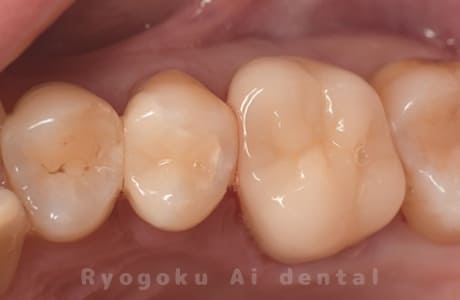

Case08

-

- 原因

- 虫歯

- 治療内容

- セラミックインレー

- 治療費用

- 77,000円

奥歯の黒い点が気になるということで来院された患者さんです。白い詰め物を外したところ、虫歯が中で大きく広がっていたため、患者さんと相談し、セラミックインレーで治療を行いました。

<リスク・副作用>

過度の咬合や衝撃で割れることがあります。